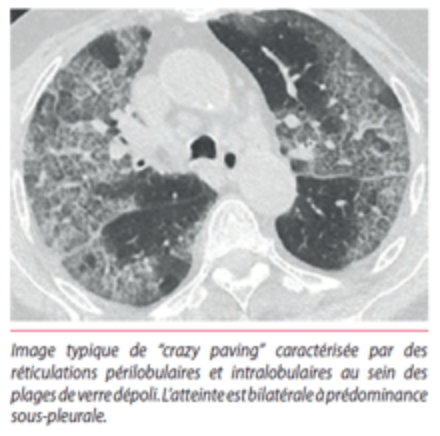

W ARDS, patologii leżącej u podstaw COVID-19, narządem dotkniętym chorobą są płuca, co skutkuje obrazowaniem:

Pęcherzyki płucne są wypełnione powietrzem, (Kolor czarny na obrazie tomografii komputerowej.

Abnormalny skan tomografii komputerowej.

OSTRZEŻENIE, te ilustracje nie są specyficzne dla COVID-19! Widzimy je w przypadkach pneumopatii naciekowej, w tym ostrej hipoksemicznej śródmiąższowej pneumopatii, która może być obecna przy krwotokach wewnątrz pęcherzyków płucnych, pneumopatiach polekowych (amiodaron), toksycznych pneumopatiach i chorobach układu, a także przy zapaleniu naczyń. Należą one do grupy patologii płuc zgrupowanych pod ogólnym terminem ARDS.

Zmiany wyglądające jak zamarznięta, matowa szyba są typowe dla ARDS, a nie dla jakiejś szczególnej przyczyny.

Występują one w szczególności w zakaźnym zapaleniu płuc z tak zwanymi atypowymi zarazkami, takimi jak Mycoplasma Pneumoniae, Chlamydia Pneumoniae czy Legionella Pneumophila, ale także w niezakaźnych pneumopatiach.